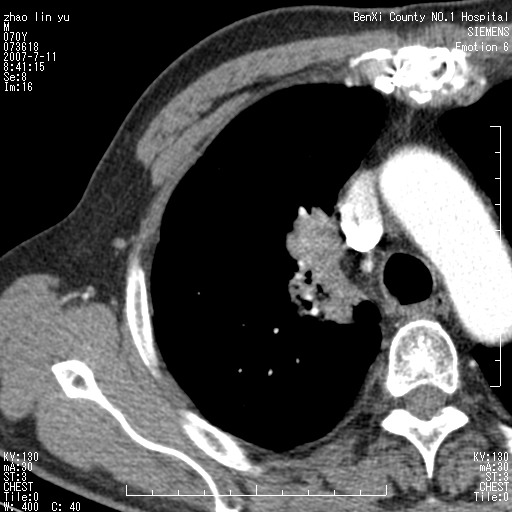

以下是引用王靖旗在2007-7-10 17:12:00的发言:[br] 男、70、咳嗽两个月,半年前换瓣手术,胸片未见异常,于昨天行x片发现右肺上野大片影,行ct扫描,这里是减薄图像,余肺正常。明天晚上会有增强扫描片,到时我会上传。[br][br] 冠状位请大家细看,应该是有意义的,[br][br] 请大家先看平扫发表意见。[br][br]

以下是引用zhangzhongshou在2007-7-10 21:43:00的发言:[br]右肺上叶周围型肺癌,以孤立型细支气管肺泡癌可能性大。